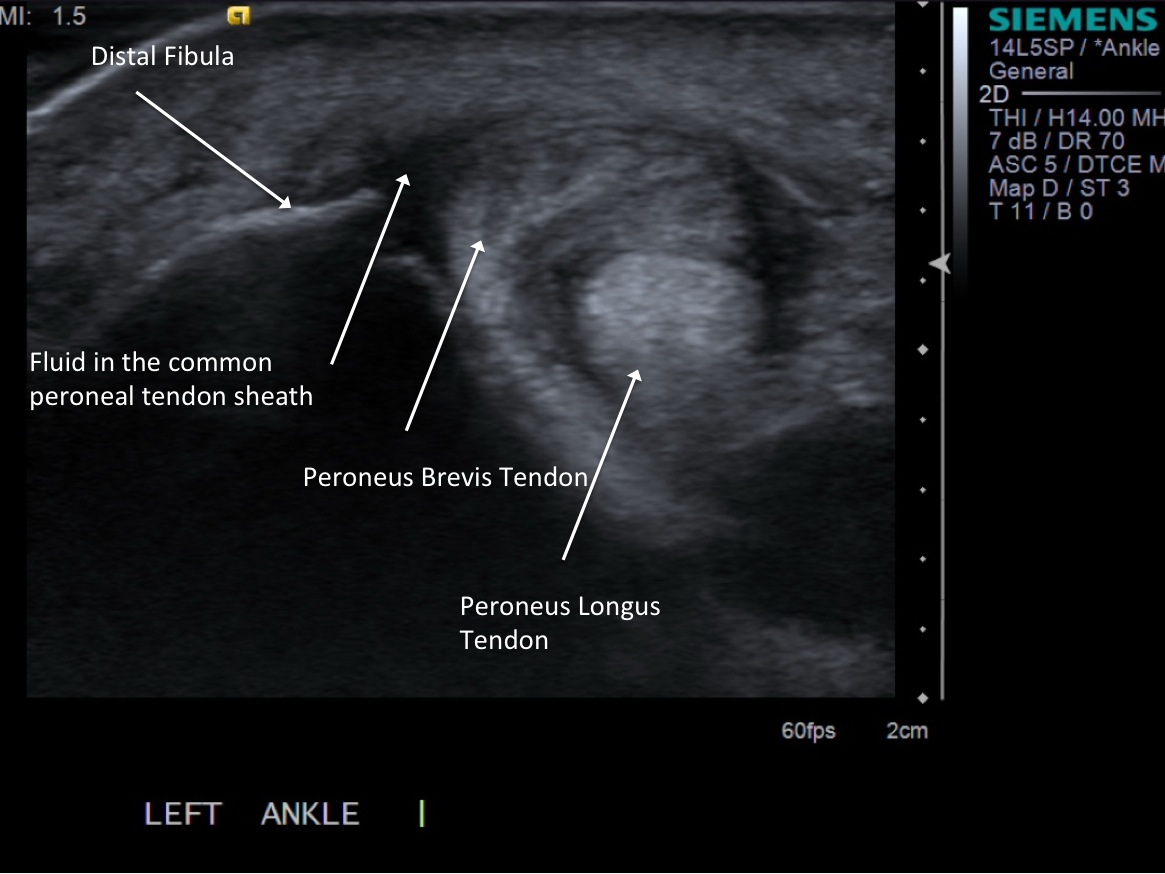

• probe: 14Mhz Linear or hockey stick probe depending on injection

3. Place probe in short axis over the peroneal tendon sheath.